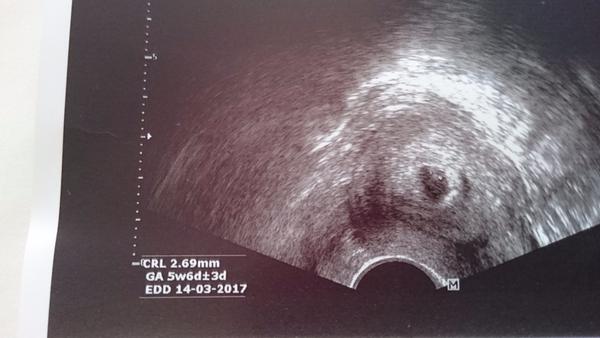

ahojky, tak já byla na UTZ minulé pondělí, dle MS jsem byla v 5.tt, doktor teda říkal,že to vypadá na 4.tt a je to taky taková malá tečka, foto přikládám: